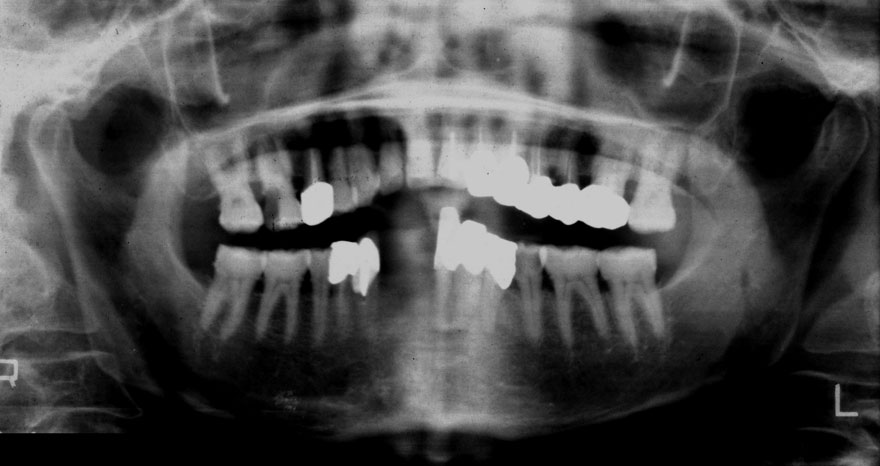

初診時 62歳 女性 平均歯槽骨喪失量:3.98mm

22年後 86歳

平均歯槽骨喪失量:4.03mm

22年間喪失量:-0.05mm

年間喪失速度:-0.002mm

(ケア頻度:1.12ヵ月ごと)

初診時 63歳 女性 平均歯槽骨喪失量:3.55mm

23年後 86歳

平均歯槽骨喪失量:3.71mm

23年間喪失量:-0.17mm

年間喪失速度:-0.007mm

(ケア頻度:1.20ヵ月ごと)